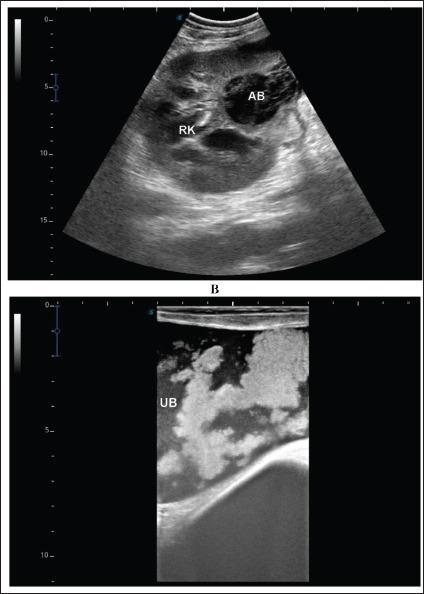

The signs of diseased camels included general gradual and/or progressive weakness, inappetence or anorexia, passage of dry feces, dysuria, bloody feces, lameness, bloody urine, and abdominal pain. Neutrophilic leukocytosis is the most significant hematological abnormality. Significant biochemical alterations included hyperproteinemia, azotemia, hyperglycemia, and increased serum alkaline phosphatase activity. Single or multiple renal abscesses were visualized sonographically compressing the renal parenchyma. Three abscesses measuring 5.2-15.0 cm were scanned in 2 camels; one affected the left and the other affected the right kidneys. In addition, two abscesses were imaged in 2 camels; both are affecting the left kidney. However, single abscesses measuring 3.6-14.0 cm in length were recorded in the remaining 13 camels; nine in the right and four in the left kidneys. The contents of the abscesses were hyperechogenic in 8 cases, hypoechoic in 4, isoechoic with hyperechoic foci in 3 cases, and heterogenous in 2. In 4 of the 17 diseased camels, hyperechoic urine and echogenic deposits were found within the urinary bladder. Bacteriological examination showed pure growth of in 10 coagulase-negative isolates, in 5 coagulase-positive isolates, and 2 unidentified species.

患病骆驼的体征包括全身逐渐和/或进行性虚弱、食欲不振或厌食、排干粪、排尿困难、血便、跛行、血尿和腹痛。中性粒细胞增多是最显著的血液学异常。显著的生化改变包括高蛋白血症、氮质血症、高血糖和血清碱性磷酸酶活性增加。超声检查可见单个或多个肾脓肿压迫肾实质。在2只骆驼中扫描到3个大小为5.2 - 15.0cm的脓肿;1个影响左肾,另1个影响右肾。此外,在2只骆驼中成像了2个脓肿;均影响左肾。然而,在其余13只骆驼中记录到单个长度为3.6 - 14.0cm的脓肿;9个在右肾,4个在左肾。脓肿内容物在8例中为高回声,4例为低回声,3例为等回声伴高回声灶,2例为不均匀回声。在17只患病骆驼中的4只,膀胱内发现高回声尿液和回声沉积物。细菌学检查显示10株凝固酶阴性分离株中纯培养物为[具体细菌名称未给出],5株凝固酶阳性分离株中为[具体细菌名称未给出],2株未鉴定的[细菌种类未给出]。